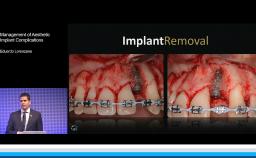

Biological and Technical Complications in Implant Dentistry

This lecture gives an excellent introduction to and overview of the wide range of complications seen in implant dentistry. Biologic and hardware complications are defined and their incidence presented. Risk factors for complications are discussed and ranked, and strategies for their management are introduced. Finally, the evolution in occurrence of complications is discussed and related to changes in available implant materials as well as to changes in surgical and prosthetic techniques.